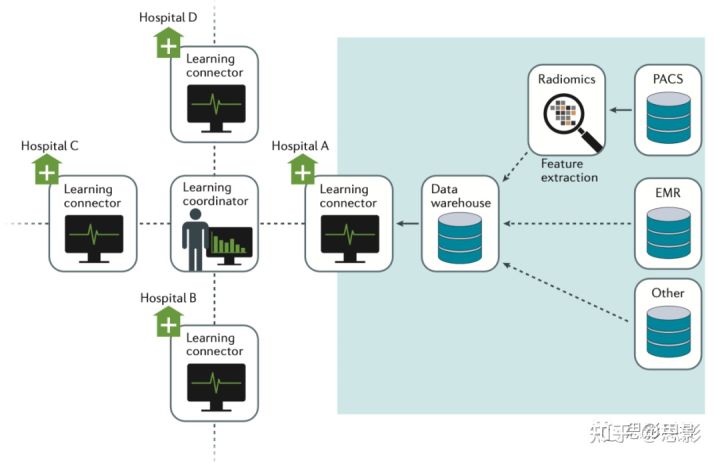

实现这一目标的一个举措是CancerLinQ,即ASCO数据集中方法。另一项倡议是worldCAT,它包括一种新的数据联合方法,成功地将荷兰、德国、比利时、意大利、丹麦、澳大利亚、中国、印度、南非、爱尔兰、英国、美国和加拿大的影像治疗机构连接起来(图6)。其他重要链接包括:癌症成像档案(TCIA)、定量成像网络(QIN)、定量成像生物标记物联盟(QIBA)和癌症定量成像:细胞过程与治疗的联系(QuIC-ConCePT).

图6,CAT系统示意图

多个中心通过学习连接器连接。连接器是机器学习算法(从学习协调器发送)从本地数据学习模型的接口连接。值得注意的是,隐私敏感信息仍保留在该研究所。合作伙伴的网站分布在荷兰、德国、比利时、意大利、丹麦、澳大利亚、中国、印度、南非、爱尔兰、英国、美国和加拿大。该系统由开源信息通信技术组合而成,可以通过SQL查询本地传递数据,或通过SPARQL端点传递到更广泛的CAT网络。CAT:计算机辅助诊断性电子病历;电子病历;PACS:图像存档和通信系统;SPARQL;简单协议和RDF查询语言。